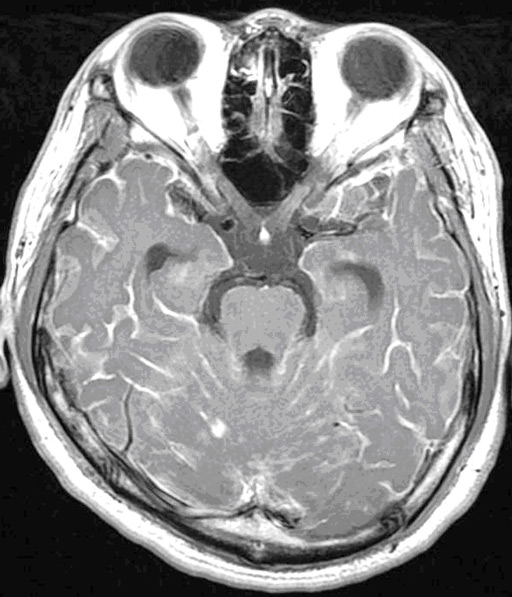

No.71症例1:20歳代男性

- 【主訴】

- めまい、右上下肢の痺れ、異常言動

- 【現病歴】

- 2ヶ月前より浮動感あり、今回上記症状にて神経内科受診。

- 【画像】

- 頭部単純CT、頭部MRI(単純、造影)、頸髄MRI(単純、造影)。

図4 MRI T2強調横断像 図4 MRI T2強調横断像

図7 MRI T2強調横断像 図7 MRI T2強調横断像